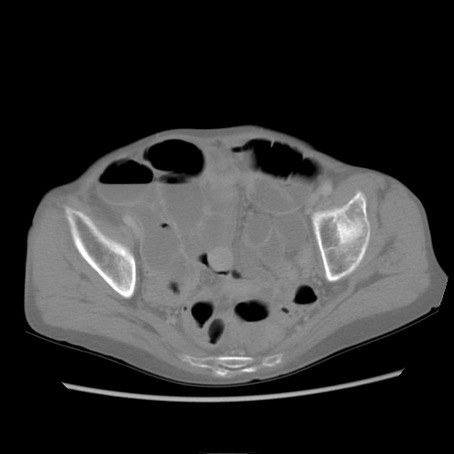

冠状断像